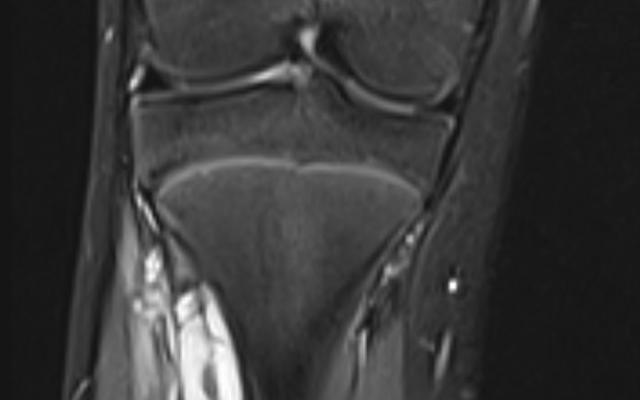

Dit artikel is alleen beschikbaar als PDF.Lees de PDF Artikelinformatie Online verschenen op 18 maart 1909 Citeer dit artikel als Ned Tijdschr Geneeskd. 1909;53:1214 Heb je nog vragen na het lezen van dit artikel? Check onze AI-tool en verbaas je over de antwoorden. ASK NTVG Ook interessant Beeldquiz Een meisje met een klapvoet Diagnose in beeld Een meisje met een klapvoet Klinische praktijk Verworven klapvoet Meer gerelateerd … Reacties Login om een reactie te plaatsen